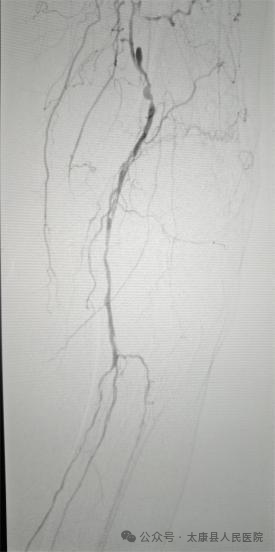

术前造影

94岁的老奶奶因下肢疼痛、足趾发黑坏死被紧急送至我院。经检查发现,其左下肢股浅动脉存在长达30厘米的完全闭塞,下肢严重缺血导致足趾坏疽,若不及时干预,不仅面临截肢风险,更可能因感染危及生命。高龄、基础病复杂、血管条件极差……重重难关让救治难度陡增。